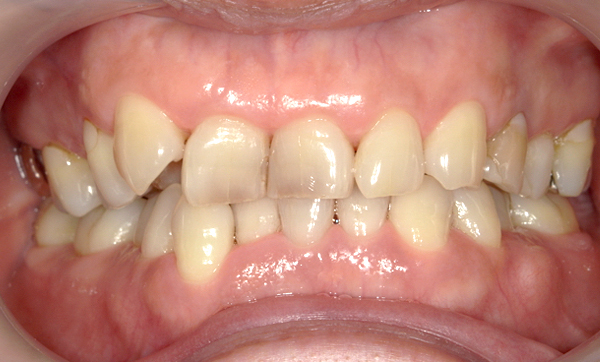

症例_016 上下顎の部分矯正

治療期間:8ヶ月金額:48万円+税50代女性八重歯捻転歯前歯のガタガタ